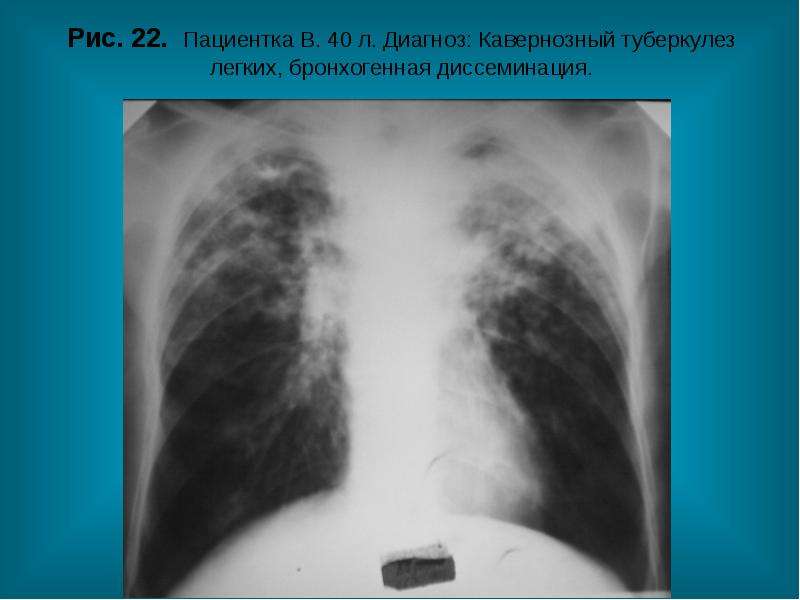

Рентгенологические изображения и синдромы патологии легких

Раздел: Кадры-подсказки